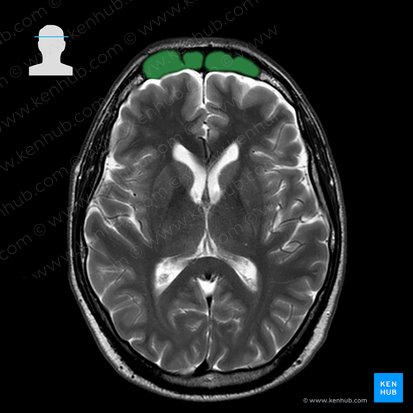

Frontal sinus

The frontal sinuses are paired air-filled cavities in the frontal bone of the skull and one of the four different paranasal sinuses, along with the maxillary sinus, sphenoidal sinus and ethmoidal air cells. They are the most superior of these sinuses and typically appear triangular-shaped. The frontal sinus, like the other paranasal sinuses, is lined by a respiratory mucus membrane which produces a film of mucous. Drainage of the sinus to the nasal cavity is via the frontonasal duct, opening into nasal cavity either at the anterior part of the middle meatus by the ethmoidal infundibulum or medial to the hiatus semilunaris.

Location Paired sinuses in the frontal bone, deep to the superciliary arches

Function Warm and humidify air, lighten skull, enhance speech resonance